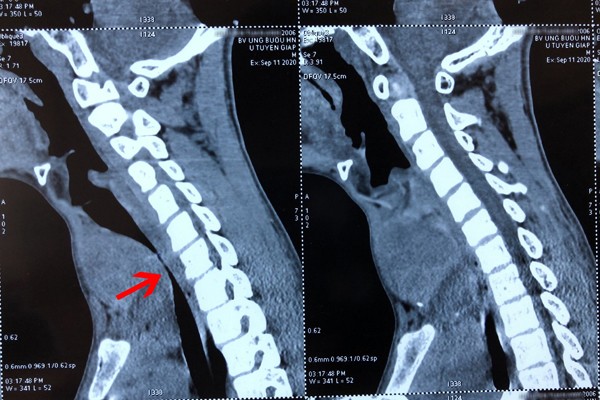

Qua hình ảnh chụp chiếu, bác sĩ xác định khối u thùy giáp trái đã di căn phổi đa ổ, lan xuống hõm ức, kích thước 8x9cm đè ép khí quản lệch hẳn sang phải gây hẹp lòng khí quản, đường kính khí quản chỗ hẹp nhất còn 4mm, nhỏ bằng 1/3 người bình thường, đây cũng là nguyên nhân khiến bệnh nhi khó thở nghiêm trọng. Ngoài ra, khối u còn khiến giọng nói của A. bị khàn, ăn uống khó khăn.